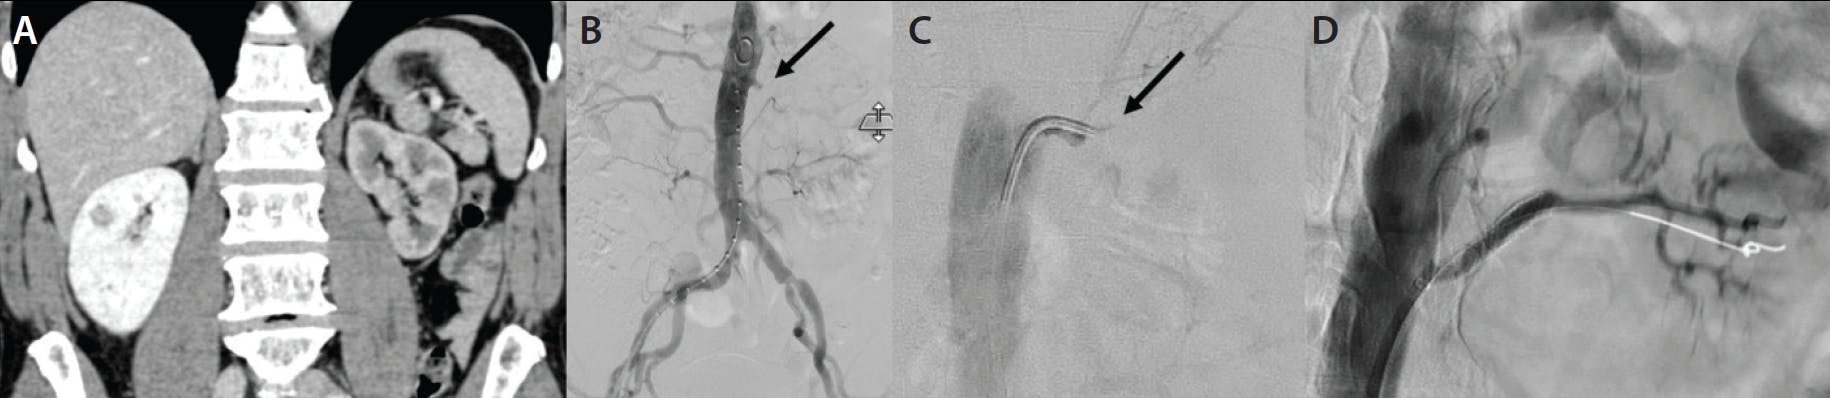

A man in his mid 60s presented to the emergency department with acute left flank pain and severe hypertension (212/167 mm Hg). Contrast-enhanced abdominal CT showed proximal occlusion of the left renal artery and poor left kidney perfusion (Figure 5A). An abdominal aortogram and selective left renal angiogram revealed total occlusion of the left renal artery (Figure 5B and 5C). The coaxial combination of a long sheath, a 5-F diagnostic catheter, and a 2-F microcatheter provided enough support for a 0.016-inch Glidewire GT-R microwire to cross the total occlusion after other microwires failed (Figure 5D). The renal artery revascularization with a 6 X 37mm Express™ balloon-expandable stent (Boston Scientific Corporation) resulted in blood pressure normalization and abdominal pain control.

Figure 5. Contrast-enhanced abdominal CT showing a proximal occlusion of the left renal artery and poor left kidney perfusion (A). Abdominal aortogram (B) and selective left renal angiogram (C) showing total occlusion of the left renal artery (arrows). The 0.016-inch Glidewire GT-R microwire crossed the total occlusion (D).